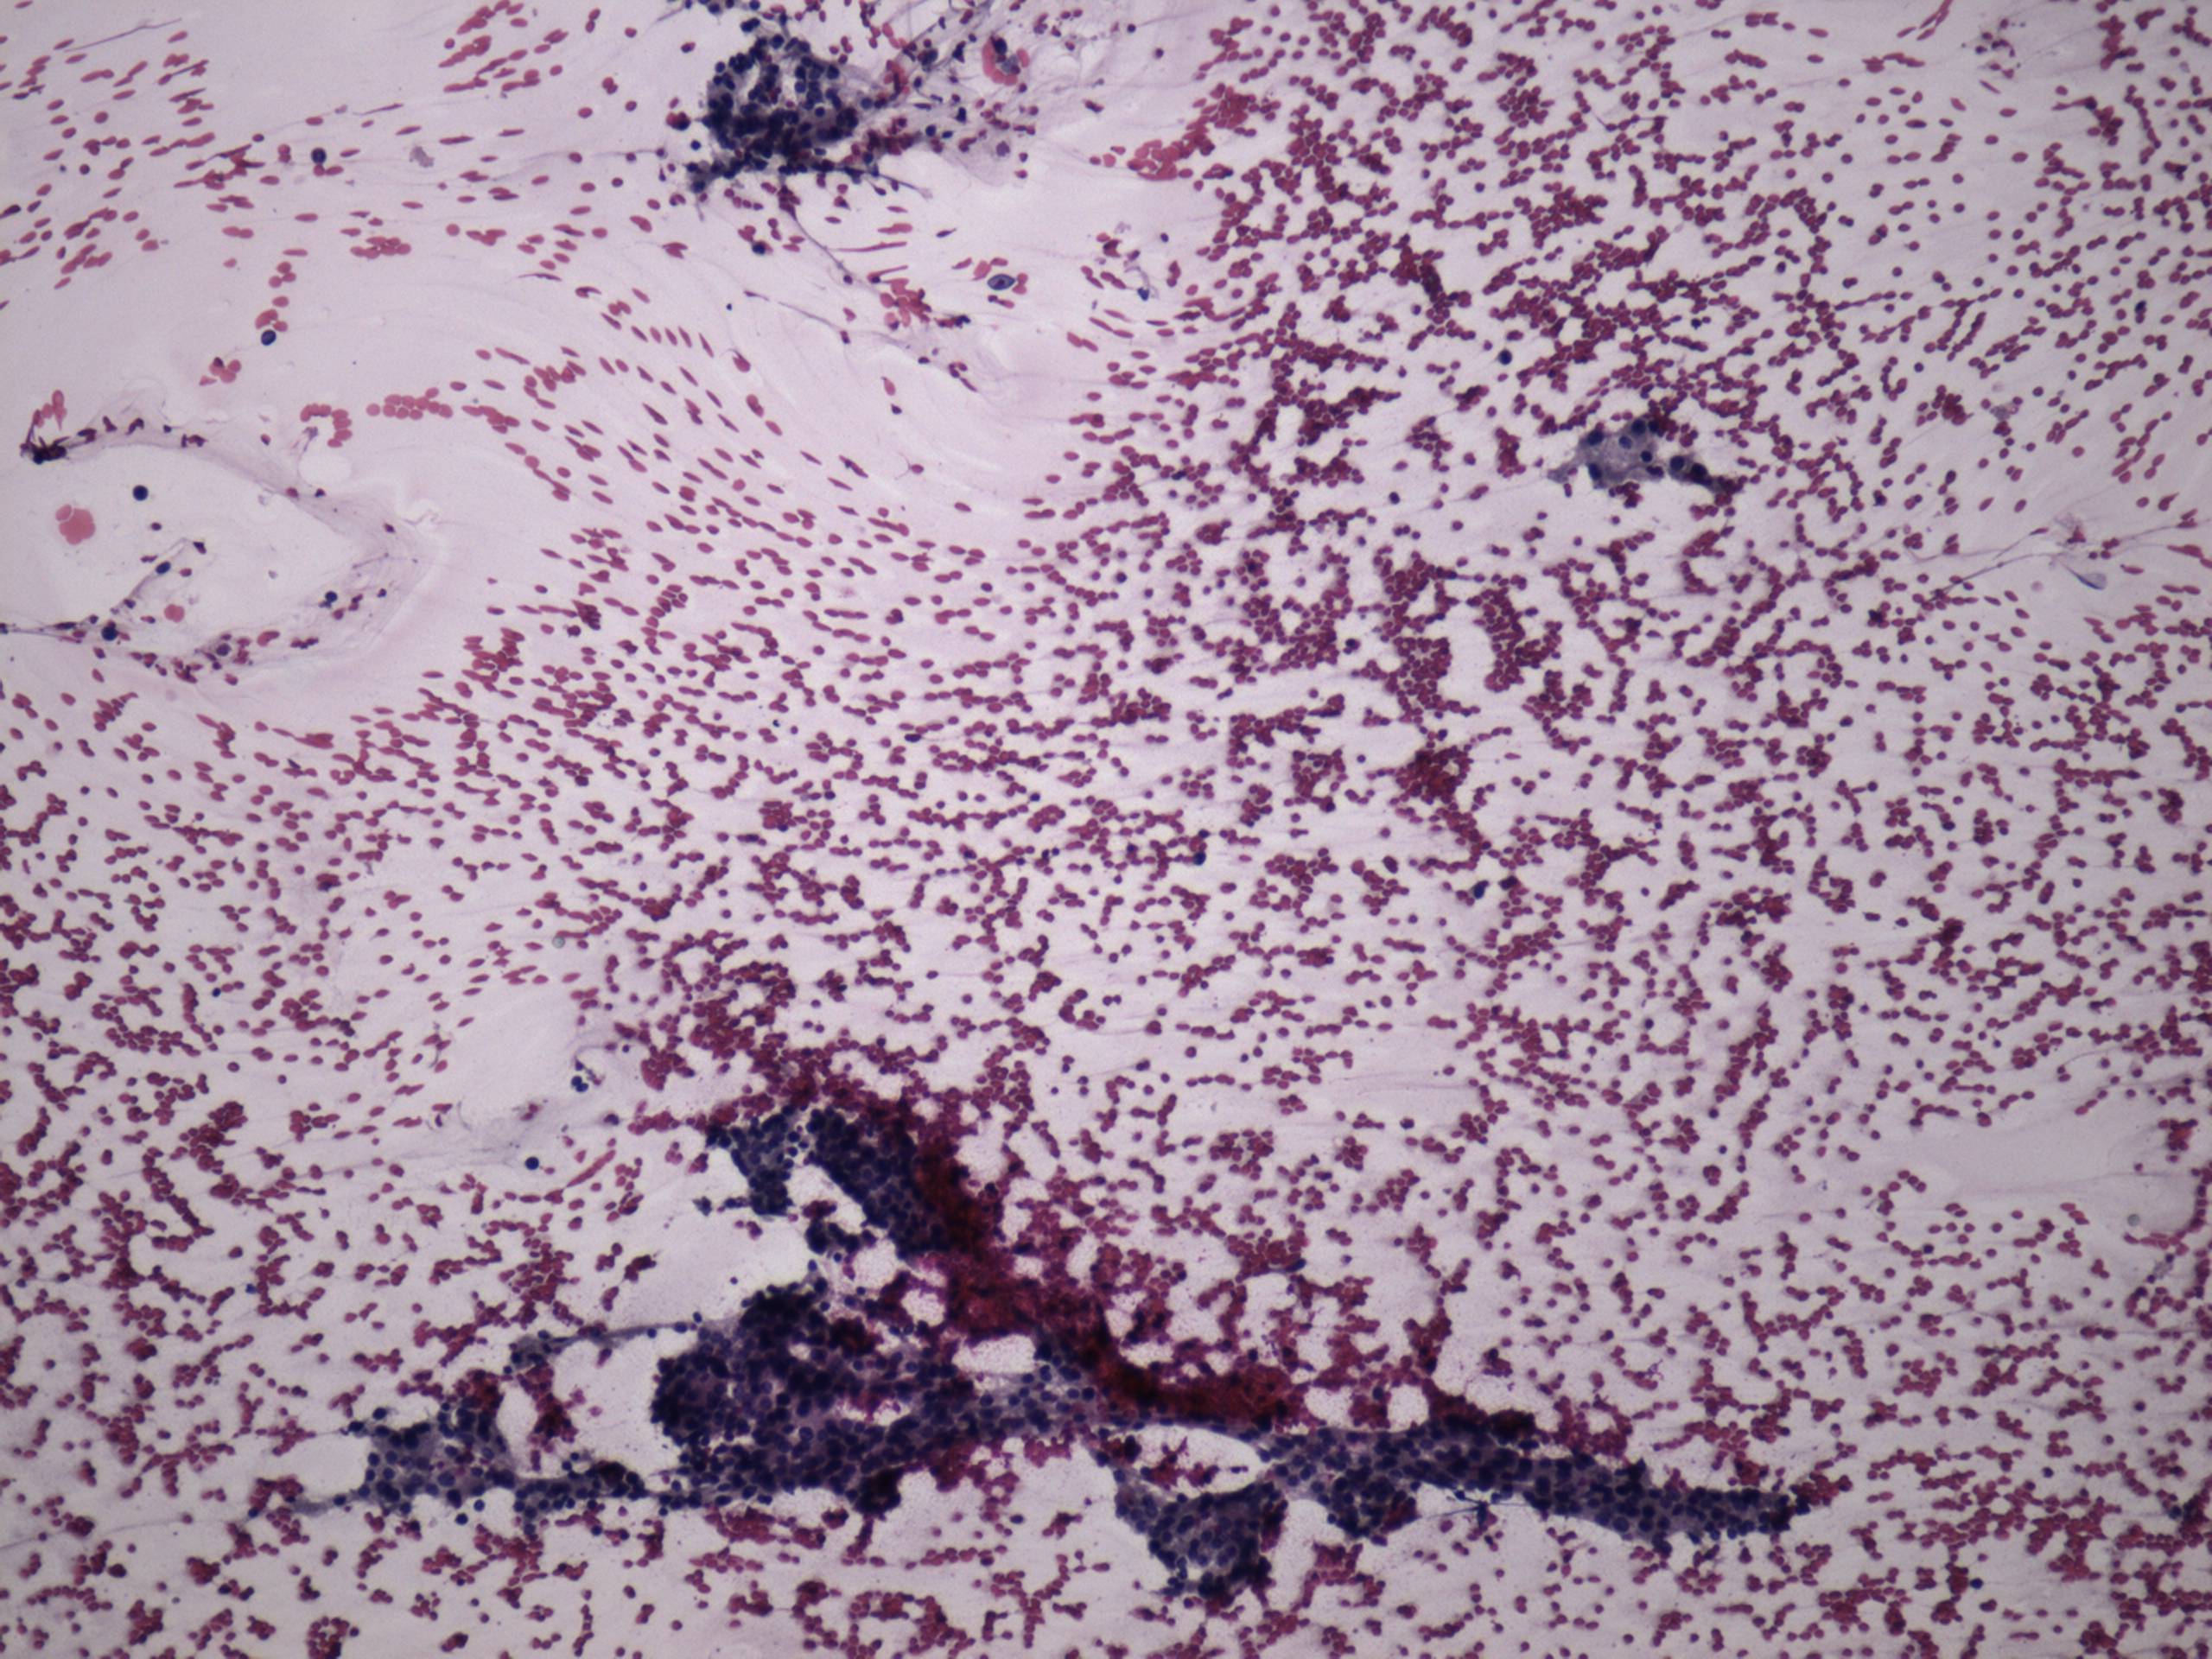

Pap-smear, 100x.   There is no colloid in the background. Epithelial cells are in loose clusters.